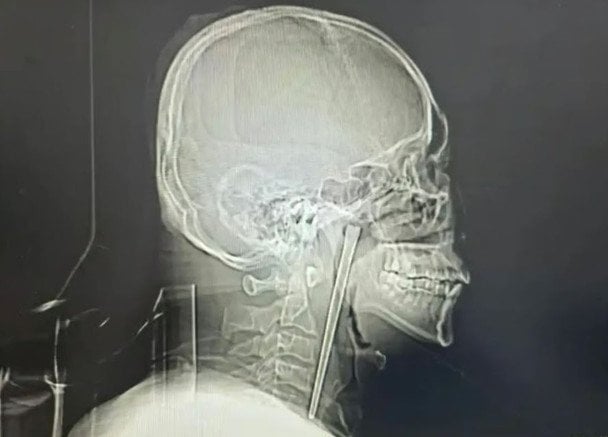

У Китаї чоловік протягом восьми років жив із металевою паличкою довжиною 12 см, яка застрягла в його горлі. Лише нещодавно її вдалося видалити під час операції.

Під час обстеження медики виявили сторонній предмет у м’якому піднебінні. Попри тривалий час перебування, паличка не спричинила серйозних ушкоджень — голосові зв’язки працювали нормально, а навколишні тканини залишилися відносно неушкодженими.

З огляду на побажання пацієнта лікарі провели малоінвазивну операцію через рот, уникнувши розрізу шиї. У результаті вдалося успішно видалити металеву паличку довжиною 12 см.